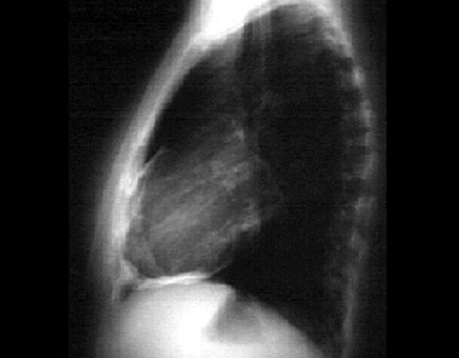

PA and Lateral

Click on the X rays to enlarge them.

Choose the best interpretation of the chest X rays:

Pericardial effusion

Normal

Lung mass and pericardial effusion

Pericardial calcification

Pericardial cyst